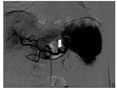

入院后予输注悬浮红细胞、抑酸护胃、补铁等治疗,患者未再出现呕血、黑便,大便隐血试验阴性。胃镜检查示十二指肠乳头处活动性渗血(图2)。腹部增强MRI检查示:①轻度肝硬化,轻度脂肪肝,动脉期肝脏异常强化灶,考虑异常灌注,左肝小囊肿。②脾大,脾部分梗死考虑,脾静脉显示不清,胃前方侧支形成;脾静脉与肠系膜上静脉汇合处血栓形成可能;脾动脉瘤。③考虑慢性胰腺炎。④胆囊底壁稍厚,胆囊腺肌症可能;右肾小囊肿。遂在介入科行脾动脉瘤栓塞术。术中见脾动脉局部囊袋样凸起,直径约8 mm,未见明显造影剂外溢,使用可控弹簧钢圈和栓塞胶进行栓塞(图3)。术后造影检查显示脾动脉主干及其远端分支显影良好,脾动脉瘤未见确切显示。患者术后多次复查血常规,血红蛋白水平维持在90 g/L以上。后复查胃镜示十二指肠乳头仍有活动性出血。遂行超声胃镜检查,内镜下见胃底、胃体上段多条曲张静脉,部分成团、成球样改变(图4A);十二指肠乳头结构无特殊,其开口可见墨绿色胆汁溢出;超声胃镜检查见胰腺实质回声不均匀,散在较密集点片状高回声区,呈云朵样;胰管显示,管壁回声增粗、增强;胆总管显示,胰头段胆管壁增厚;胰腺尾部见一3.0 cm×1.9 cm无回声区(图4B),部分囊壁呈片状增厚;脾脏显示增厚。诊断:慢性胰腺炎;胰尾部囊性病变,性质待定;重度胃底静脉曲张。对症支持治疗后患者未再解黑便,复查血红蛋白水平稳定,患者拒绝进一步检查,要求出院随访。

2018年2月11日,患者因"再发黑便1周"再次入住浙江大学医学院附属邵逸夫医院消化内科。查血常规示红细胞计数为1.84×1012/L,血红蛋白为34 g/L,平均红细胞体积为65.9 fL,平均血红蛋白水平为279 g/L。胃镜检查示十二指肠乳头搏动性出血,中重度胃底静脉曲张。胃镜下乳头冲洗后间断可见黄绿色胆汁流出,考虑胰管来源出血可能性大。急诊腹部增强CT检查示脾动脉瘤复发,行急诊脾动脉造影术和脾动脉栓塞术,脾动脉局部可见造影剂外溢,考虑活动性出血(图5);超选栓塞后造影见破裂口处闭塞,远端脾动脉通过侧支部分代偿,术中证实为脾动脉瘤破裂入胰管引起消化道出血。病情稳定后出院,随访5个月患者未再发呕血、黑便,复查血红蛋白水平在正常参考值范围内,大便隐血阴性。